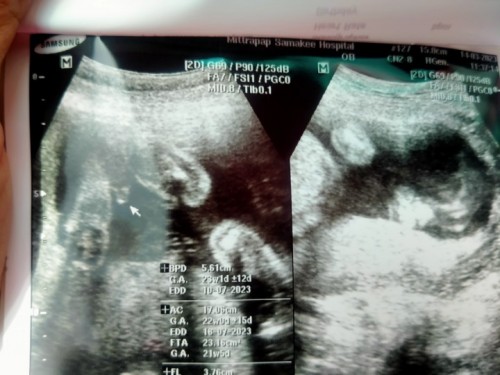

อัลตร้าซาวด์

วันนี้ไปซาวด์มา หมอว่าได้ ผช. แม่ๆช่วยดูหน่อยได้ชายแน่ใช่ไหม แอบกลัวๆ พอซื้อของไว้เดี๋ยวจะเป็น ผญ.